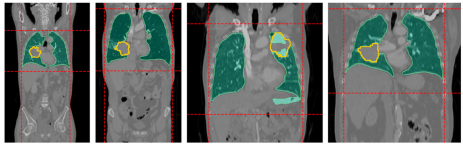

比较基线模型LLS与引入胸廓约束的LLSB,DSC提升5.4%至74.6%,证明该预处理能有效聚焦感兴趣区域。图示案例显示,传统肺掩模(绿色)会遗漏胸膜附近病灶,而红色虚线所示的胸廓边界框成功捕获全部目标。